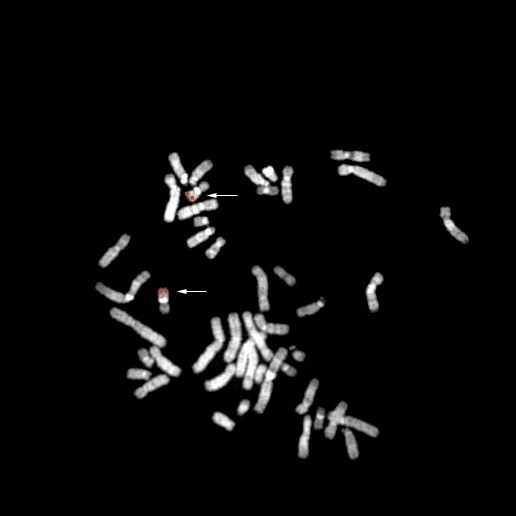

bA467I17